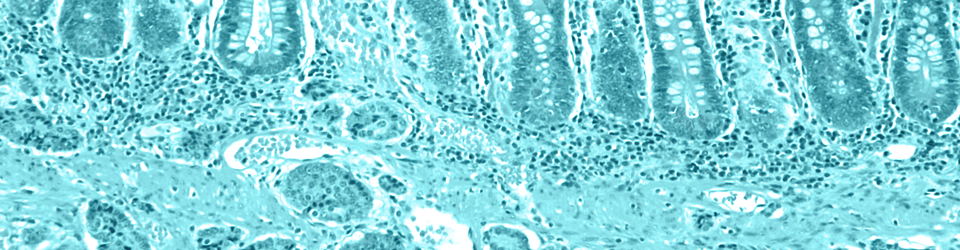

There are several types of NETs, and terms such as “high-grade” or “poorly differentiated” are used to describe the rare and aggressive form of cervical cancers that are the focus of DamnCancer.*  The high-grade designation refers to how these tumors act – they grow very quickly and have a tendency to spread to other organs within the body.  These aggressive NETs are called poorly differentiated because they look very different from the surrounding tissue when viewed under a microscope. High-grade (or poorly differentiated) NETs, while still quite rare, are more commonly found in other parts of the body, such as the pancreas, the gastrointestinal tract and the lungs. Low-grade, well differentiated NETs, also called carcinoids, may be either benign or part of a chronic condition one can live with for many years.

Of the <2% of cervical cancers made up of high-grade (or poorly differentiated) neuroendocrine tumors, most cases are Small Cell Cervical Cancer (abbreviated throughout this website as SCCC), with the remainder being Large Cell Cervical Cancer.  The names are based once again on how the cancer cells look under a microscope, and while their appearances differ, they behave and therefore are treated similarly.